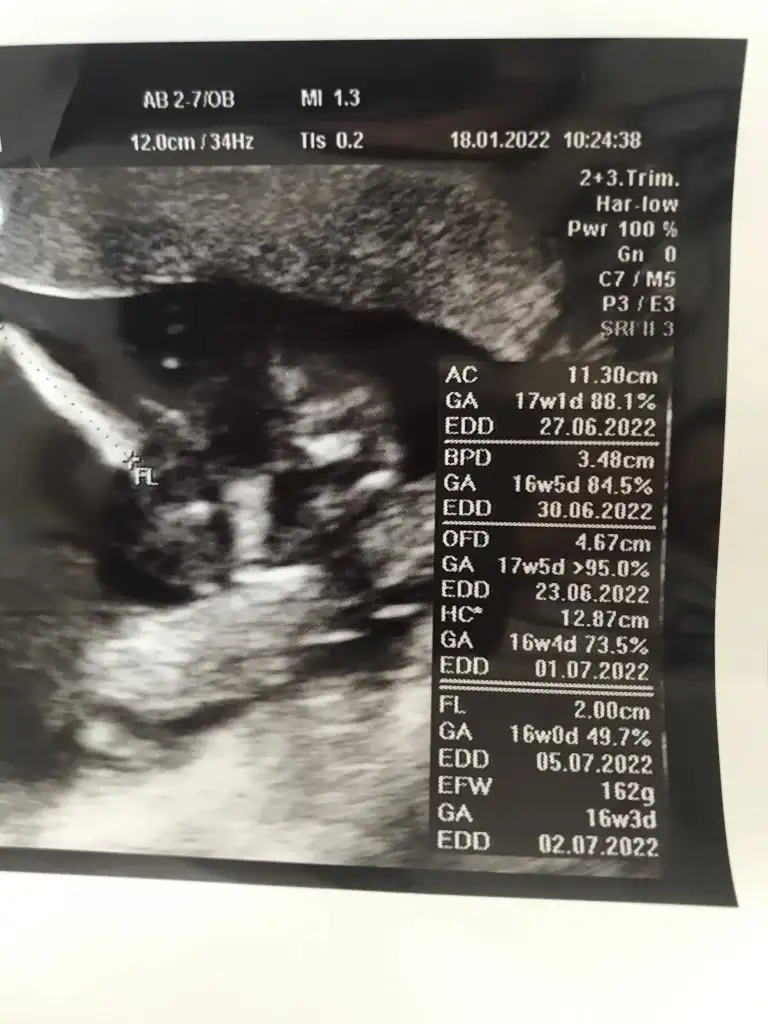

Benim hep 3 hafta ilerdeydi 39 cm dogdu gayet normalBir de bu haftalardan sonra ultrasonda parça prça bakılıyor o nedenle karın ve kafa ölçüsüne göre hafta belirleniyor ya benimkinin kafa bir hafta ilerden gidiyor normal midir ki? Herşey yolunda dedi doktor ama Eki Görüntüle 2991017